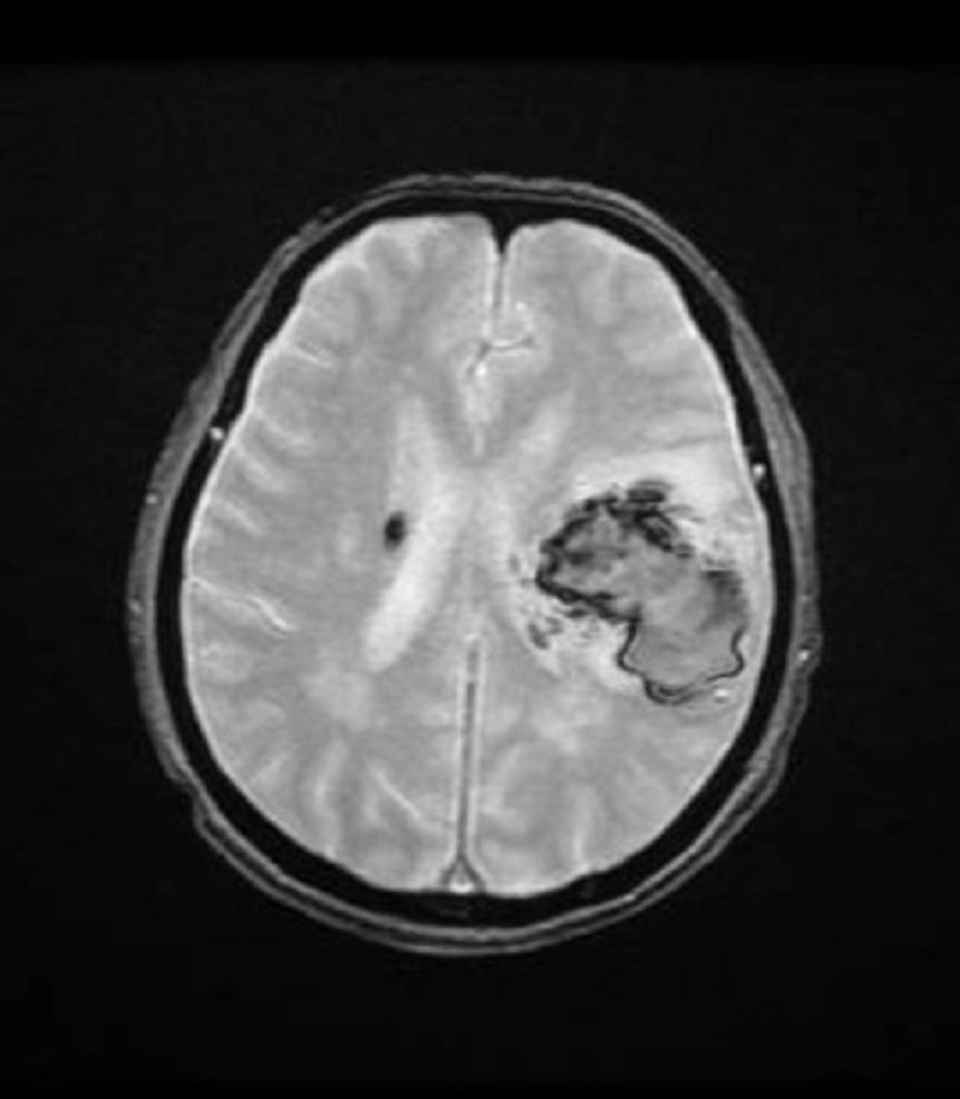

Các kết quả chẩn đoán hình ảnh cho thấy, người bệnh bị xuất huyết não bán cầu trái với lượng máu khoảng 40ml gây hiệu ứng choán chỗ. Sau hội chẩn, các bác sĩ đã chỉ định cho bệnh nhân can thiệp phẫu thuật bằng phương pháp xâm lấn tối thiểu và gây tê tại chỗ (bệnh nhân sẽ hoàn toàn tỉnh táo vì không thực hiện phương pháp gây mê).

BS Chu Tấn Sĩ cho biết, sau khi gây tê toàn bộ da đầu, bệnh nhân được đặt khung cố định đầu, tiến hành phẫu thuật với hệ thống robot sử dụng công nghệ trí tuệ nhân tạo. Bằng hệ thống định vị hình ảnh 3D chụp cộng hưởng từ khuếch tán, sức căng công nghệ trí tuệ nhân tạo sẽ tự động xử lý để thấy các bó dẫn truyền thần kinh. Nhờ đó, các bác sĩ sẽ tùy chỉnh tối ưu để tiếp cận tổn thương trong phẫu thuật. Bên cạnh đó, hệ thống lập trình phẫu thuật được tích hợp vào phần định vị cho phép phẫu thuật viên lập kế hoạch tối ưu nhất khi phân tích các bó sợi thần kinh quanh tổn thương.